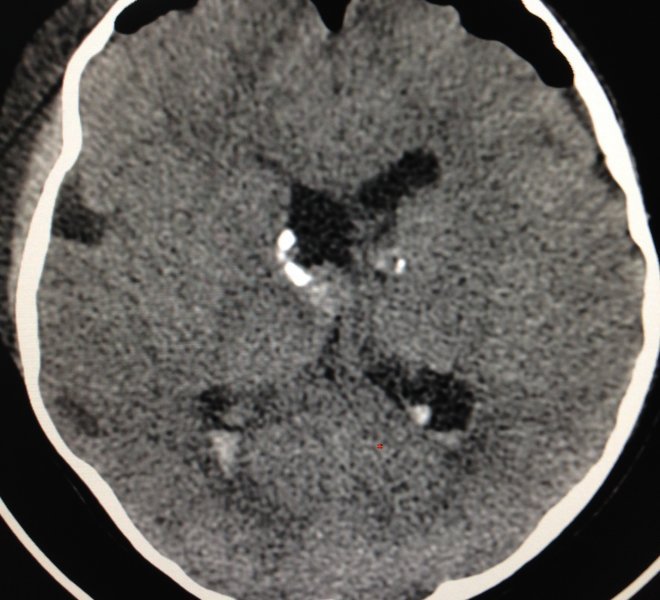

ESCLEROSIS TUBEROSA